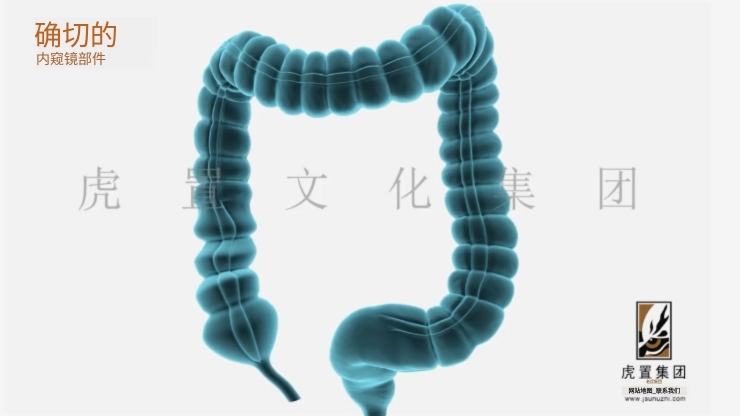

深耕于数字设计及展示领域的虎置文化集团成立20年,正努力成为全球知名的数字设计及展示服务商,为客户提供设计、展示及施工的一站式服务,为不同行业客户提供基于文化创意服务的整体解决方案。设计包括:建筑设计、景观设计、规划设计、展馆设计、室内设计、BIM设计;展示包括:三维动画、全息展示、影视广告、数字展馆、二维动漫、3D仿真效果图、VR&AR、企业宣传片等;施工包括:展馆展厅、室内装饰、幕墙工程、亮化工程。

公司依靠先进的三维动画制作技术,致力于三维动画的定制和制作,为数百家企业制作了各种类型的三维动画,有着丰富的实践经验和服务水平,制作的三维动画具有更灵活的表现形式、更强大的说服力和更生动的效果,成为众多企事业单位宣传产品、拓展市场、塑造品牌影响力的重要工具。服务政府、部队、世界五百强企业百余家;服务“一带一路”、“中国 制造2025”等重大国家战略项目;服务美国斯坦福、上海同济大学等国内外知名高校。